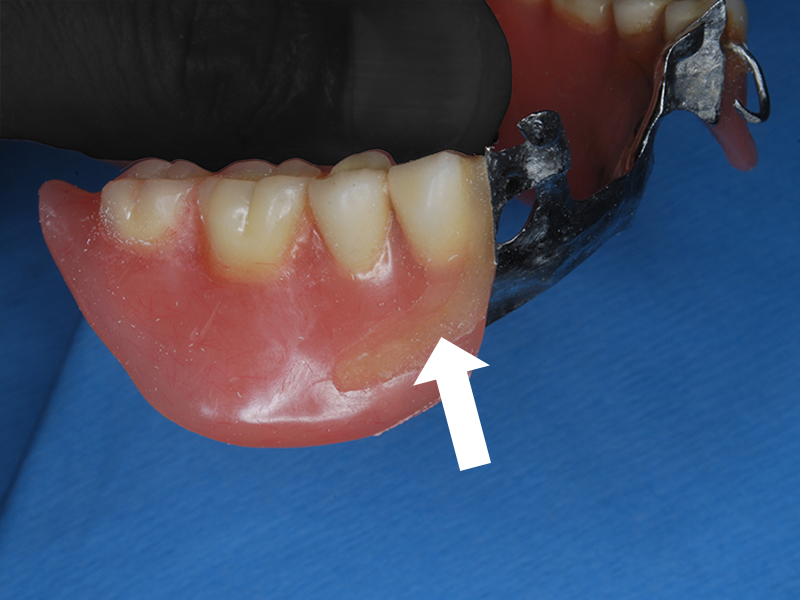

義歯維持装置(クラスプ)の欠けた部分

修理部分に凹みをつけ装着して型を取る